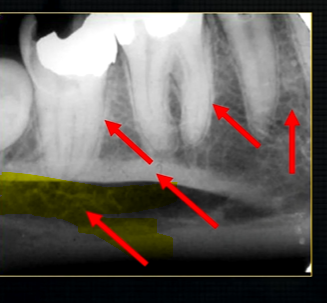

periapical radiograph → posterior maxilla

radiolucent maxillary sinus and radiopaque floor

radiopaque shadow cast by zygoma, hollowed out by maxillary sinus

lower end of the dense, zygomatic bone

posterior aspect of the maxilla - smooth round tuberosity

this was taken using the bisected angle technique

x ray beam was directed below the zygoma

very lower of the zygoma is seen - projected above the apices

pterygoid hammulus - supports the muscles of the soft palate

coronoid process of the mandible